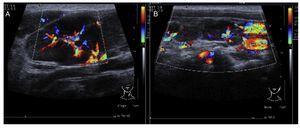

In the ultrasound of the cervical region carried out on February 23, 2012, there were multiple adenopathies identified on the right side of the lymph node chain. The Doppler effect showed a higher vascular flow and displacement of the adjacent vascular paths. On the left side there were lymph nodes >1 cm in size and similar to the right side showing a greater vascular flow in its center (Fig. 1). Simple chest x-ray of November 19 showed normal characteristics. Only a volume increase in both cervical regions in relation to lymph node growth was identified (figure not shown).

Figure 1 Ultrasound image in the cervical region bilaterally. Multiple adenopathies are observed at this level which, according to the Doppler effect, showed an increase of the flow within. (A) Left side. (B) Right side.